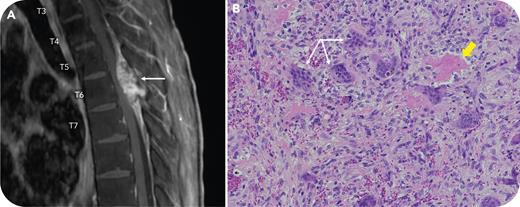

A 25-year-old man with a rare hemoglobin variant (Sallanches), previously confirmed by α-globin gene sequencing demonstrating a homozygous mutation at codon 104 and a transfusion-dependent α-thalassemia phenotype, presented with lower extremity weakness. Pretransfusion hemoglobin levels were typically ∼60 g/L and our approach had been to transfuse only when the patient had symptoms attributable to anemia, which was about 4 times per year. Magnetic resonance imaging (panel A) revealed a cord-compressing mass (17 × 33 × 8.5 mm) at the T6 vertebral body (arrow). There was concern for extramedullary hematopoiesis (EMH), and surgery was undertaken. Pathology (panel B: hematoxylin and eosin stain; original magnification ×40) revealed a giant cell–rich (arrows) lesion, with fibrosis and bone (thick arrow) negative for pancytokeratin, epithelial membrane antigen, glial fibrillary acidic protein, and progesterone receptor, as revealed by immunohistochemistry. The findings were most consistent with a solid-variant aneurysmal bone cyst, a diagnosis confirmed by a fluorescence in situ hydridization stain positive for ubiquitin-specific peptidase 6.

Although patients with α-thalassemia are less likely than those with β-thalassemia to develop EMH, this patient was transfusion-dependent and, as such, at risk for EMH. However, in this case, surgical findings revealed a benign solid-variant aneurysmal bone cyst. The absence of evidence for EMH obviated the need for more aggressive intervention or alteration of our conservative transfusion strategy predicated on preexisting secondary hemochromatosis.